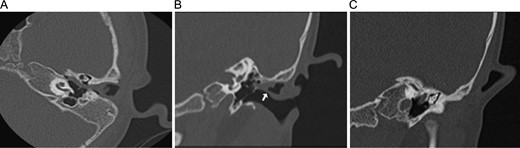

Final pathologic examination (Fig. 3) showed dense fibrous tissue with focal benign glands as well as ectopic salivary gland tissue with overlying excoriation.

Hematoxylin and eosin (H&E) stained micrographs of the specimen. (A) Low power H&E of the specimen, showing areas of fibrosis (between arrows) and glandular tissue composed of serous and mucinous cells typical of submandibular salivary gland (surrounded by dotted line). (B) Higher power H&E shows the salivary glandular tissue with connection to the surface (bottom portion of image) and overlying ciliated columnar epithelium (at top of image). (C) High power H&E shows the admixture of cell types with the darker granular serous cells and the pale blue mucinous cells.